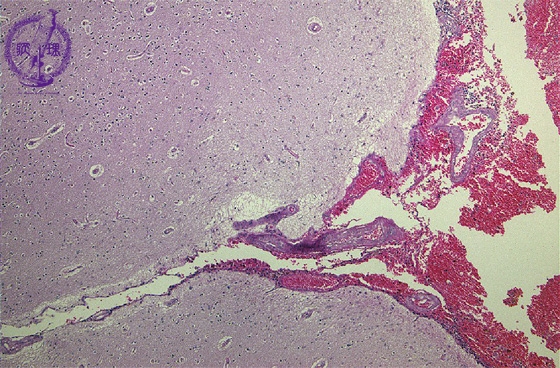

Microscopic findings (H.E. low magnification): Extensive hemorrhage was identified in the subarachnoidal space, but not in the brain parenchyma.